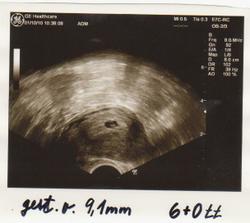

Taááákže 2. KET při 3. IVF